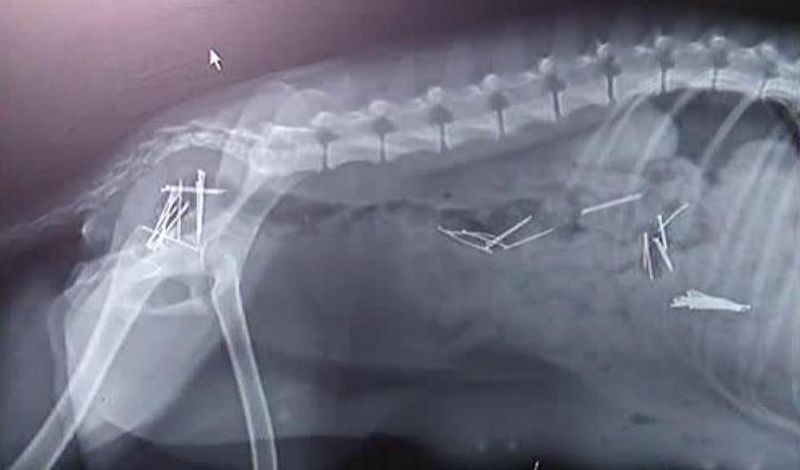

Un act de cruzime cum nici măcar medicilor veterinari nu le-a mai fost dat să vadă vreodată vine din judeţul Arad! O femeie e acuzată că a încercat să-şi omoare câinele punându-i în mâncare 45 de ace cu gămălie! ##VIDEO28213##

Desi proprietara neaga, vecinii o contrazic. Catelusa cu stomacul plin cu ace de gamalie ar fi a ei, iar tot planul diabolic l-ar fi pus la cale ca sa se razbune ca a ramas gestanta. In loc sa o fi sterilizat, femeia ar fi infometat-o, ca sa fie sigura ca bietul animal va inghiti mancarea cu ace.

"A vazut ca este gestanta si a dus-o la clinica, pentru sterilizare si dupa sterilizare au si deparazitat-o si catelusa a vomitat ace de gamalie”, spune medicul veterinar.